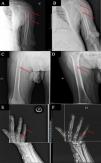

Based on these findings, β2m amyloidosis concomitant with a high remodeling metabolic bone disease was suspected. However, histologic diagnosis could not be confirmed due to the unavailability of bone tissue samples. Treatment was initiated with low-dose doxycycline and the frequency of on-line hemodiafiltration sessions was increased to four sessions per week ; the patient refused to undergo additional sessions beyond this. The patient presented a favorable clinical course, with the Visual Analog Scale decline from 9 to 6. One month after the increase in on-line hemodialysis sessions, the pre-dialysis serum concentration of β2m decreased from 41.7 to 32.2 mg/L, a decrease of 22%. After 12 months of intensified post-dilution hemodiafiltration, and 13 months of doxycycline, radiographic examination of the left humerus (Fig. 1A and B), right femur (Fig. 1C and D) and middle phalanx of the fifth finger of the right hand (Fig. 1E and F) revealed improvement and even resolution of bone lesions.